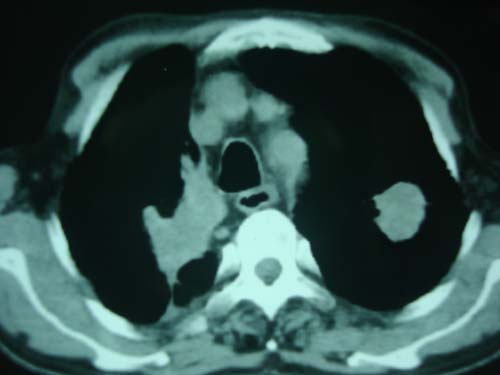

病灶有分叶,毛刺,考虑肺癌可能性大,建议穿刺。

病灶有分叶 毛刺 左侧叶裂上移 考虑肺癌可能性大 建议穿刺

右上肺结核,左上肺周围型肺癌可能性大

右分叶,右毛刺,考虑肺癌可能性大。

团块状病灶,病灶周围长毛刺及灶周肺气肿。